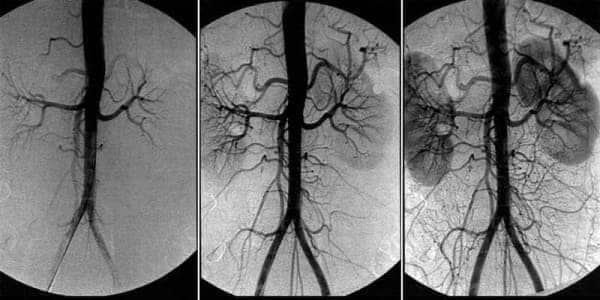

kép

Az eltömődött erek a szervezet összes létfontosságú rendszerének hibás működéséhez vezetnek.

A vérkeringés szisztémásan helyreáll - minden érben, artériában és hajszálérben.